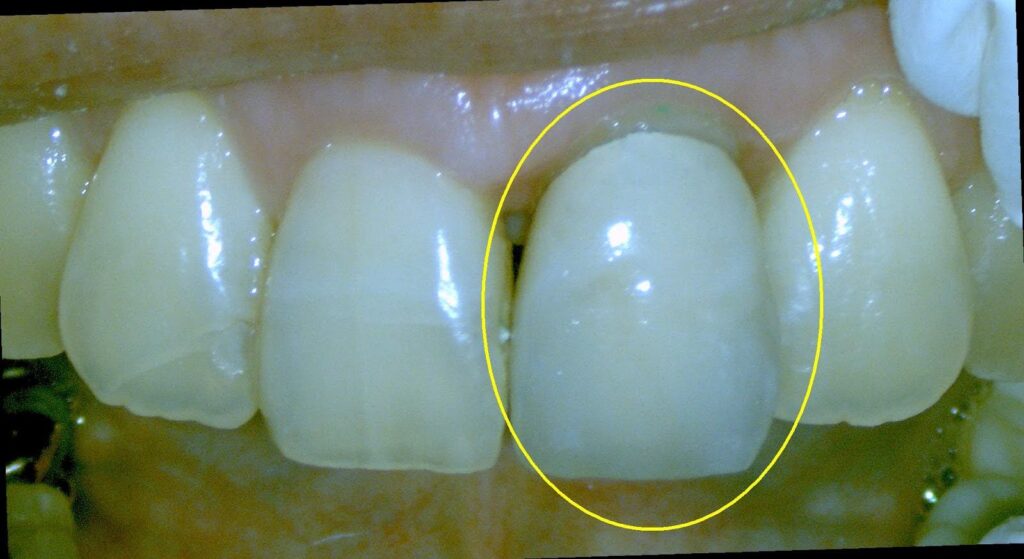

Dr.:歯の神経(歯髄)は、強打の為断絶してしまい、助かりません。かといって抜歯はしません。壊死してしまった根管内の歯髄を綺麗にする根管治療をします。

赤丸が膿んでいる病変部